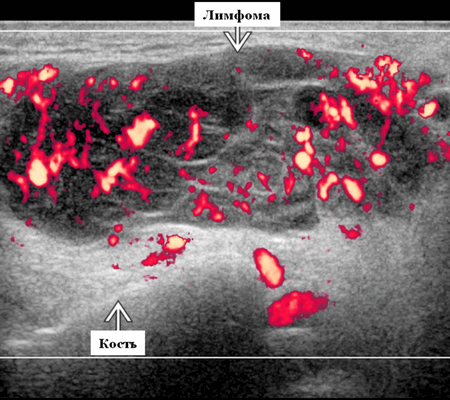

Серошкальное УЗИ. Узловая НХЛ. Одиночные или множественные увеличенные яйцевидные внутрипаротидные лимфатические узлы. Гомогенно гипоэхогенный по отношению к паренхиме околоушной железы. Сетчатый эхосигнал. Заднее акустическое усиление. Первичная паренхиматозная НХЛ. Рассеянный, неоднородный эхосигнал; нечеткие, гипоэхогенные, похожие на опухоль участки. В пунктате внутрикистозная или паренхиматозная кальцификация из-за конечной стадии воспалительного изменения. Небольшие кистозные области образуются из-за сдавления терминальных протоков лимфоидной гипертрофией. Множественные небольшие гипоэхогенные участки (представляют собой лимфоидные агрегаты), разбросанные на фоне ткани слюнной железы. Изменения могут имитировать хронический сиалоаденит и диагноз часто ставится при биопсии. На УЗИ необходимо искать аналогичное поражение других слюнных и слезных желез, фон синдром Шегрена, BLEL. Может иметь или не иметь перипаротидную и шейную лимфаденопатию

Цветной допплер. Узловая НХЛ. Выраженная центральная или внутриузловая гиперваскуляризация. Паренхима при неходжкинской лимфоме более диффузная железистая гиперваскуляризация. Васкуляризация от умеренной до выраженной в плохо очерченных образованиях.